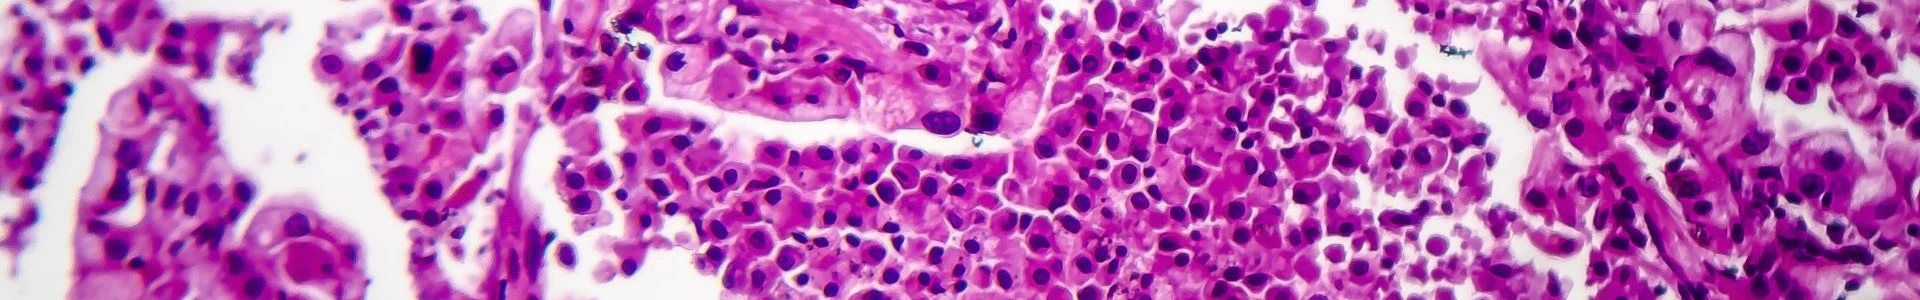

El área de enfermedades de Respirología se centra en el estudio y tratamiento de las enfermedades que afectan al sistema respiratorio. Este campo abarca una amplia gama de afecciones que afectan los pulmones y las vías respiratorias, incluidas enfermedades agudas y crónicas. La investigación en respirología tiene como objetivo comprender la fisiopatología de los trastornos respiratorios, mejorar las técnicas de diagnóstico y desarrollar tratamientos y medidas preventivas eficaces. Utilizando modelos animales avanzados, ensayos clínicos y tecnologías de vanguardia, los investigadores exploran los mecanismos de las enfermedades pulmonares y evalúan nuevos enfoques terapéuticos. Un enfoque integral es esencial para mejorar la atención al paciente, mejorar los resultados del tratamiento y mejorar la salud respiratoria.

El uso de primates no humanos (NHP) en la investigación de enfermedades respirológicas es muy ventajoso debido a su gran parecido fisiológico e inmunológico con los humanos. Esta similitud garantiza que los datos de los modelos NHP sean altamente traducibles, lo que mejora la precisión de los hallazgos preclínicos y respalda el desarrollo de tratamientos eficaces para enfermedades respiratorias como el asma, la EPOC y la fibrosis pulmonar. La compleja anatomía pulmonar y el sistema inmunológico de los NHP permiten un estudio detallado y confiable de los mecanismos de la enfermedad y las intervenciones terapéuticas, lo que los hace indispensables para mejorar la salud respiratoria humana.

La sofisticada anatomía pulmonar y el sistema inmunológico de los NHP permiten el estudio detallado de mecanismos complejos de enfermedades respiratorias e intervenciones terapéuticas, proporcionando información sólida sobre la progresión de la enfermedad y la eficacia del tratamiento.